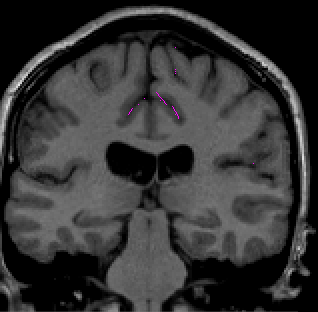

Once you have drawn your sulci lines, the insula should be clearly outlined (by little dots) in the coronal view (Fig 3). This is particularly useful in the more anterior slices.

Figure 3